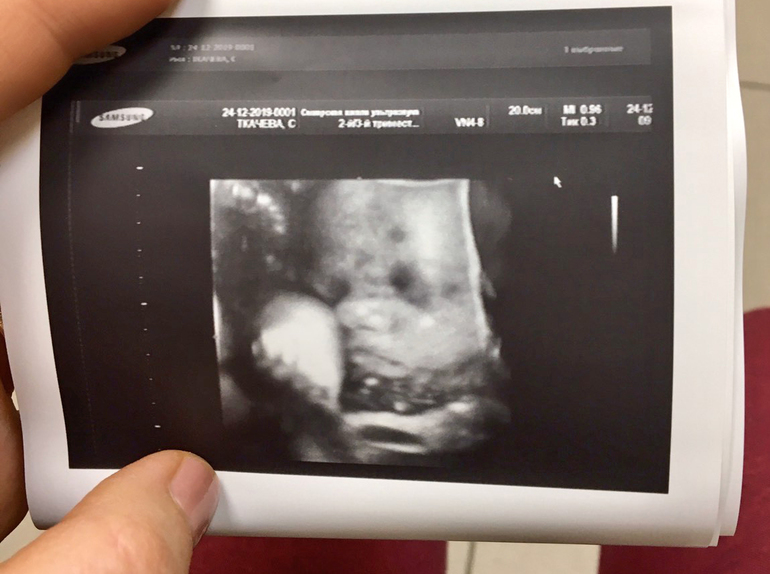

Фотогалерея (Наши пузики и детки)Осталось немножко и я стану дважды Эко-мамой!)) Пдр 19-25 января,ждем всей семьей. Сын уже больше 3кг,готовится на выход,а мама +13кг. Планирую опять рожать сама,даст Бог,хотя зарекалась-никогда!))) Не хочется расставаться с пузиком,я так кайфую быть беременной,что беременность снова пролетела незаметно. И вот уже роды на носу и всего несколько недель до встречи. А будто вчера был перенос)) 6-й по счету.